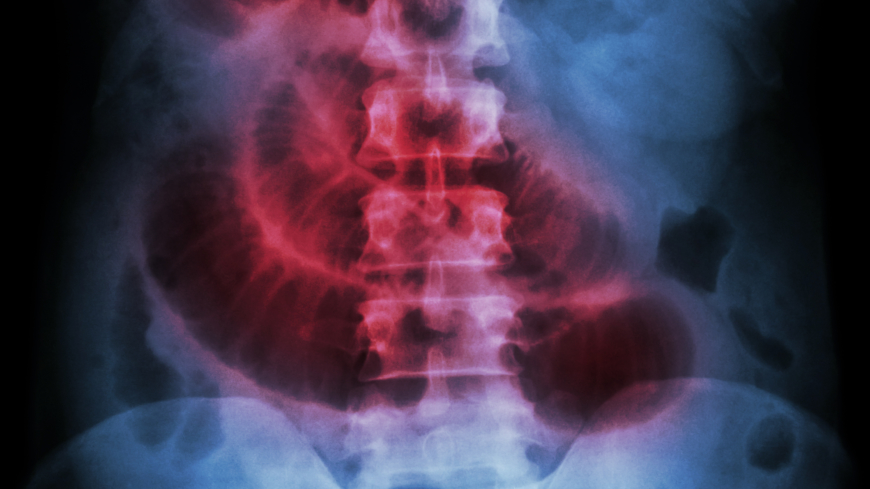

Tarmvred kan orsakas av att något fastnat i tarmen, och kan ge upphov till kräkningar och uppblåst mage.  Foto: Getty Images

För att fastställa om det är tarmvred som orsakar symtomen görs i de flesta fall en fysisk hälsoundersökning. Detta får sedan tillsammans med symtombeskrivningar och sjukdomshistorik ligga till grund för en primär bedömning. Därefter brukar antigen röntgen eller datortomografi utföras för att bekräfta misstankar om tarmvred. Om läkaren tror att något sitter fast och blockerar tarmen sövs man ibland ner så att en koloskopi kan utföras. En koloskopi innebär att en tunn slang med en kamera förs in via kolon för att se om det finns någonting som hindrar tarmrörelserna.